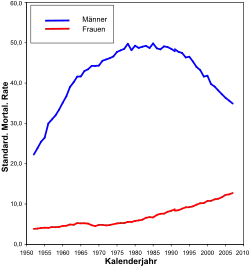

Epidemiologie

25 Prozent aller bösartigen Tumoren (Malignome) sind Bronchialkarzinome. Beim Mann ist es weltweit die häufigste Krebsart; in Deutschland nach dem Prostatakarzinom und dem kolorektalen Karzinom die dritthäufigste. Als Ursache von Krebssterbefällen liegt es bei Männern auf Platz eins, bei Frauen auf Platz zwei.[6] Die Inzidenz liegt in Mitteleuropa bei etwa 60 pro 100.000 Einwohner. Die Zahl der Neuerkrankungen – in Deutschland etwa 50.000 pro Jahr – weist eine steigende Tendenz auf. Unter den Todesursachen in Deutschland nimmt es mit rund 40.000 Todesfällen im Jahr die vierte Position ein, bei Männern gar die dritte.[7] Der Altersgipfel der Erkrankungen liegt um das 60. Lebensjahr. Die durchschnittliche Fünfjahresüberlebensrate (d. h., wie viele Erkrankte nach fünf Jahren noch leben) beträgt bei Männern 15, bei Frauen 20 Prozent.[6] Die Lebenserwartung des einzelnen Patienten ist aber sehr stark vom Stadium der Erkrankung (TNM-Klassifikation) und dem Subtypus (siehe unten) abhängig.

Eine zunehmende Häufigkeit bei Frauen wird beobachtet; auch bei Frauen in Europa wird Lungenkrebs bald die häufigste Krebstodesursache sein, in Großbritannien und Polen ist dies schon der Fall.[8] Das Verhältnis von erkrankten Männern zu Frauen liegt bei etwa 3:1, wobei es auf Grund der Änderung im Tabakkonsumverhalten von Frauen immer mehr zu einer Angleichung kommt (siehe Diagramm). Bedeutsam können Umwelteinflüsse oder genetische Ursachen sein, die Prognose ist bei Frauen etwas besser. Der Nichtraucher-Lungenkrebs ist bei Frauen häufiger als bei Männern.[9] Auch in den USA war die Lungenkrebsrate bei Männern stets höher als bei Frauen. Eine neuere Erhebung zeigt allerdings, dass bei jungen weißen US-Amerikanern die Lungenkrebs-Inzidenz bei Frauen über der von Männern liegt. Dies ist allein mit dem Rauchverhalten nicht hinreichend erklärbar.[10]